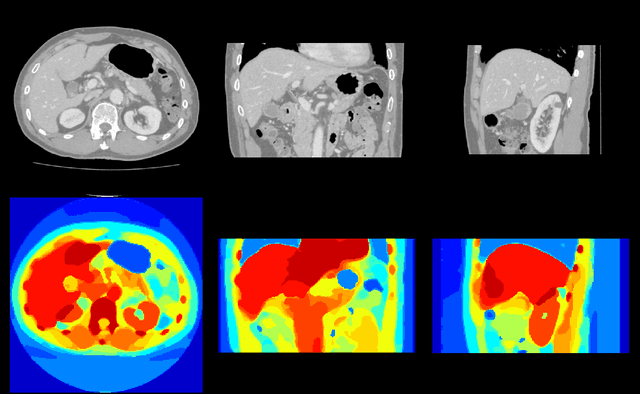

Abstract:Recent advances in deep learning led to novel generative modeling techniques that achieve unprecedented quality in generated samples and performance in learning complex distributions in imaging data. These new models in medical image computing have important applications that form clinically relevant and very challenging unsupervised learning problems. In this paper, we explore the feasibility of using state-of-the-art auto-encoder-based deep generative models, such as variational and adversarial auto-encoders, for one such task: abnormality detection in medical imaging. We utilize typical, publicly available datasets with brain scans from healthy subjects and patients with stroke lesions and brain tumors. We use the data from healthy subjects to train different auto-encoder based models to learn the distribution of healthy images and detect pathologies as outliers. Models that can better learn the data distribution should be able to detect outliers more accurately. We evaluate the detection performance of deep generative models and compare them with non-deep learning based approaches to provide a benchmark of the current state of research. We conclude that abnormality detection is a challenging task for deep generative models and large room exists for improvement. In order to facilitate further research, we aim to provide carefully pre-processed imaging data available to the research community.